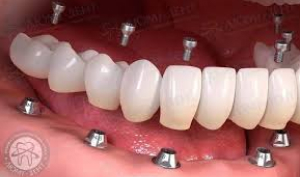

Імплантація вирішує проблему пацієнтів з повною адентією (повна втрата зубів). За допомогою постановки 4 або 6 імплантатів, можна повернути функцію і естетику повність беззубої щелепи за технологією «all on 4» або «all on 6». В нашій клініці ми використовуємо лише високоякісні системи імплантів, котрі дають надійний результат на довгі роки.